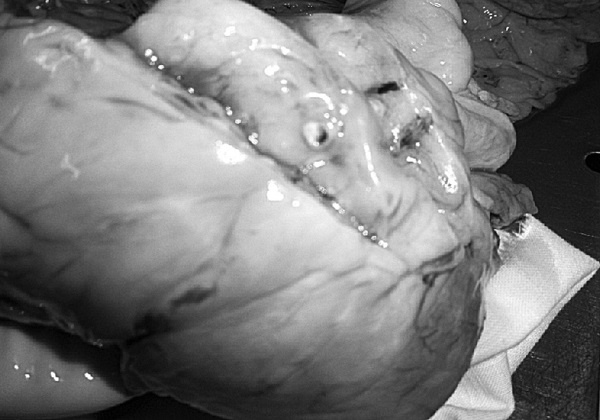

Рис. 1. Результаты аутопсии больного 68 лет

В рамках академической книги, естественно, следует выдерживать определенный стиль изложения, хотя каждому понятно, что на протяжении 12 лет практически помощи пациенту не было. Но тем не менее давайте вместе проанализируем факты, так как они изложены в амбулаторной карте. Итак, начнем с диагноза ИБС, после которого вместо определения клинической ее формы (постинфарктный кардиосклероз, хроническая аневризма и т. д.) доктор пишет морфологический диагноз: атеросклероз коронарных сосудов. В клинике этот диагноз может быть выставлен только при условии имеющейся коронарографии. Далее за 12 лет нет информации об ЭКГ, нарушениях ритма и пр. Поэтому и форму ИБС установить затруднительно, уже не говоря об отсутствии за столько времени ЭХОКГ. Но тем не менее диагноз был выставлен, были все показания для назначения обоснованной терапии. Ни обоснований, ни самой терапии в амбулаторной карте нет. В 2003 году пациент переносит ОНМК, после чего ему назначают курсами винпоцетин и пирацетам. Трудно комментировать эти назначения, поскольку нет не только доказательной базы эффективности указанных препаратов, но и обоснованных рекомендаций по их применению у больных после перенесенного инсульта. Далее с 2004 по 2007 год единичные осмотры терапевта и невролога по поводу жалоб на слабость в конечностях, головокружения и снижение памяти. Указания на иммобилизацию отсутствуют. Очевидно, что отсутствие наблюдения, медикаментозной и реабилитационной поддержки, а как вы узнаете и позже – отсутствие понимания значения маломобильности превратило существование пациента только в одно – самостоятельную борьбу за жизнь. Эта борьба была продолжена еще в течение 4 лет. Случайным осмотром отмечены трофические нарушения и отечность нижних конечностей, пролежни, снижение памяти и плохой сон. Интерпретации клинической дано не было, судить о причине отеков (сердечная недостаточность или местные кожные или сосудистые изменения) невозможно. Цифры АД не указаны (!). Но тем не менее был выставлен диагноз, в котором впервые прозвучала токсическая полиневропатия (что имелось в виду и какой токсикоз, осталось за кадром клинических мыслей врача), НК 1 и пролежни. Выписан феназепам по 0,5 мг на ночь (обещали придерживаться академизма, но выдержать сложно, цинизм в худшем его проявлении). Следующая запись через 2 месяца – констатация смерти. 68-летний пациент после смерти даже «не заслужил» посмертного эпикриза. По данным секции, у больного был очень высокий кардиоваскулярный риск (табл. 1), определяемый мультифокальным атеросклерозом, АГ и ХБП.